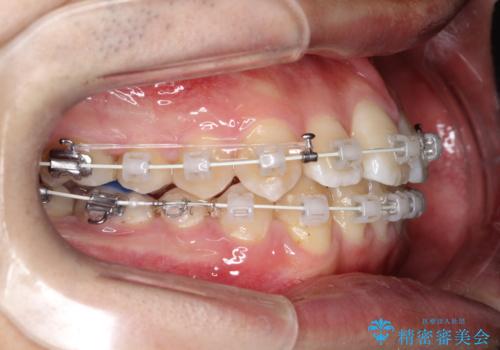

- 矯正装置

- 審美装置

- 治療期間

- 1年6ヶ月